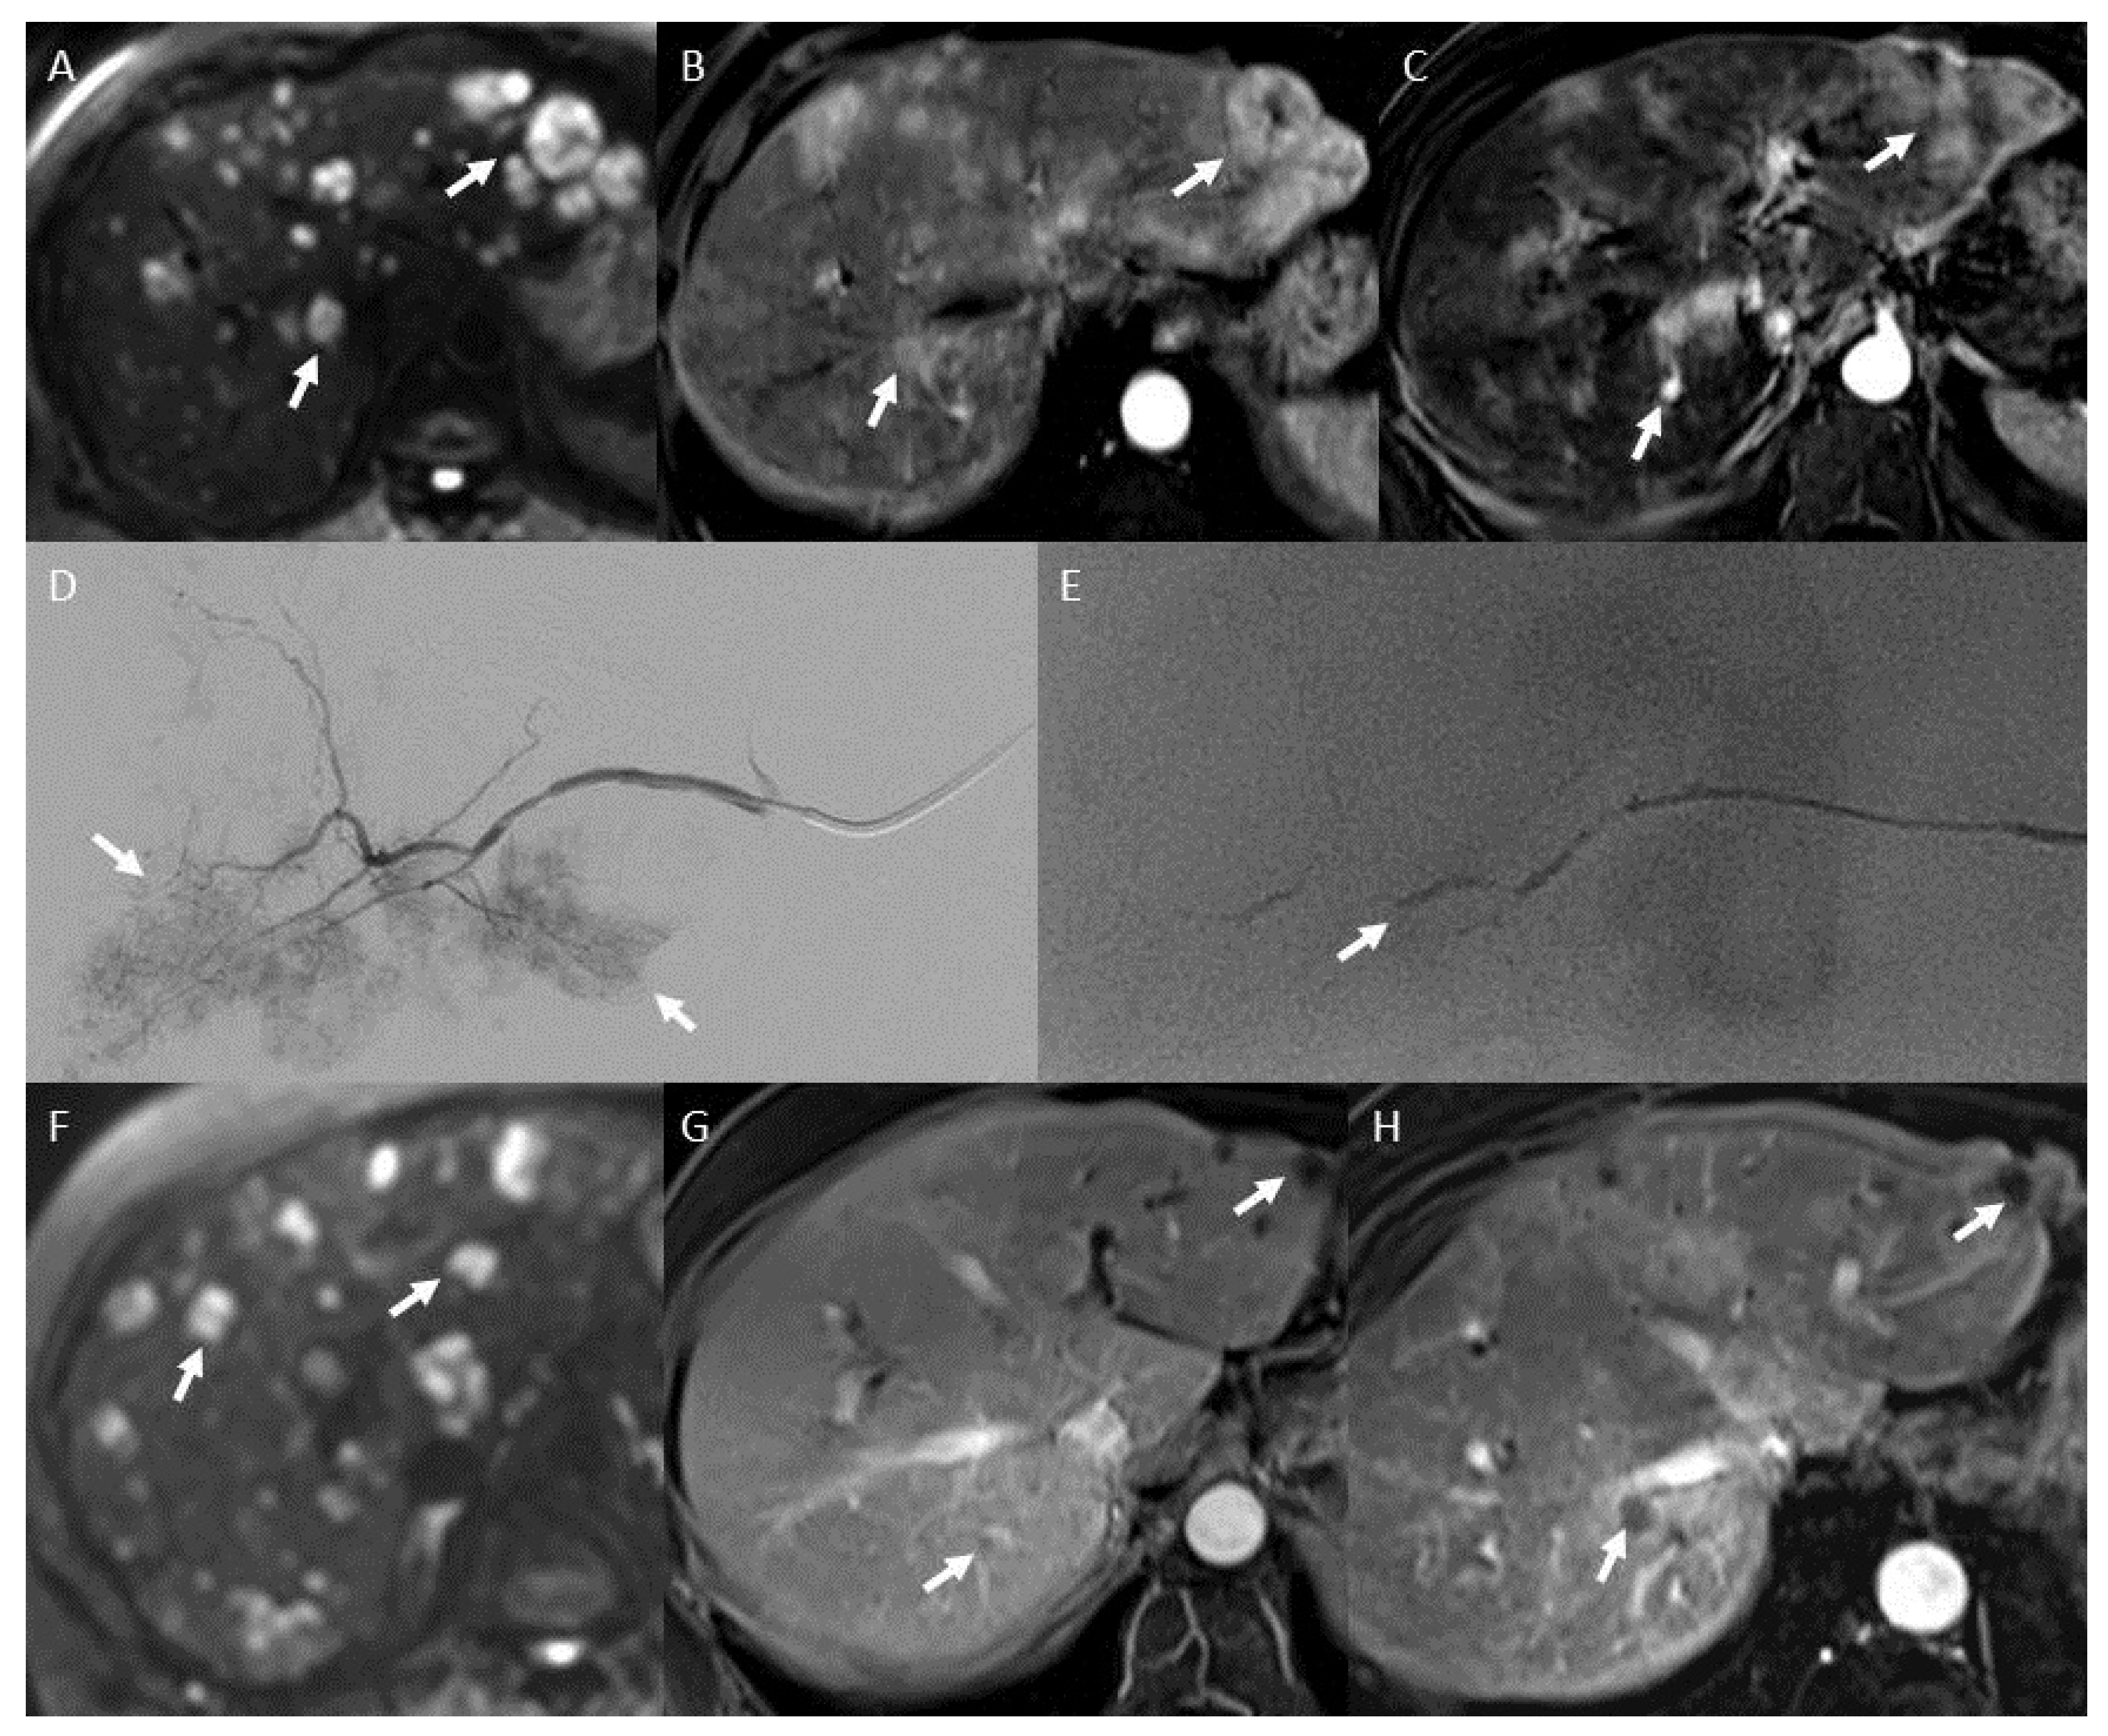

2.8.4. Pre- and Post-Treatment Imaging Prognostic Factors

3.5.2. Disease Control and Radiological Response

3.6.2. Post-Therapeutic Imaging Prognosis Factors